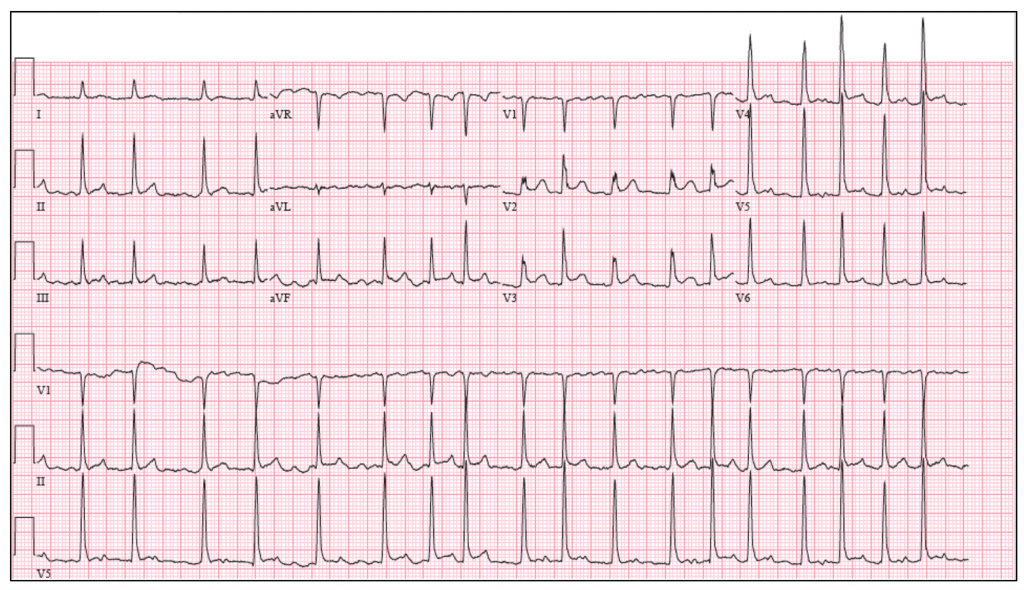

The electrocardiogram (ECG) obtained after electrical cardioversion Electrical Heart Cardioversion cardioversion is an electrical intervention to restore the heart's normal rhythm from atrial fibrillation, a common arrhythmia. cardioversion is a treatment for irregular heartbeat (afib) that uses electrical or chemical shocks to restore a normal. cardioversion puts your heart back into a normal rhythm using medicines or an electric device. Learn about the reasons, risks,. synchronized. Electrical Heart Cardioversion.